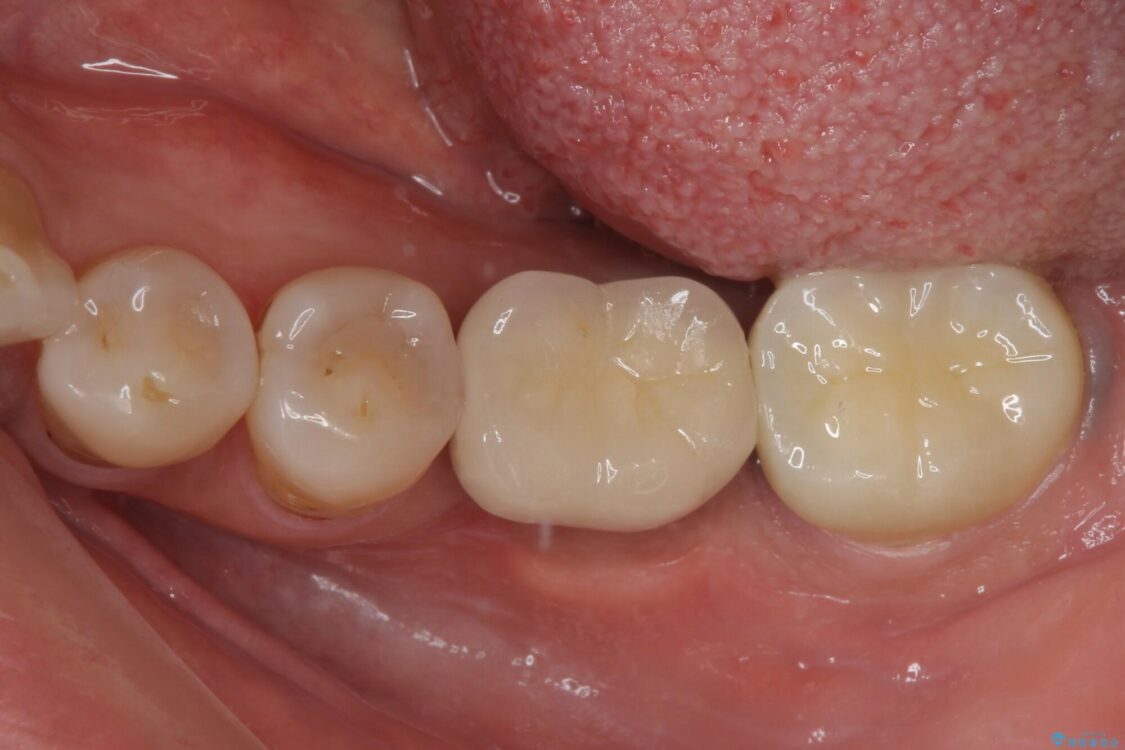

治療後

• しみる奥歯 オールセラミッククラウンによる補綴治療 治療後画像

仮歯に変えた時点でしみる症状はなくなり、オールセラミッククラウンはまるで自分自身の歯のような舌触りとなり、大変満足していただきました。